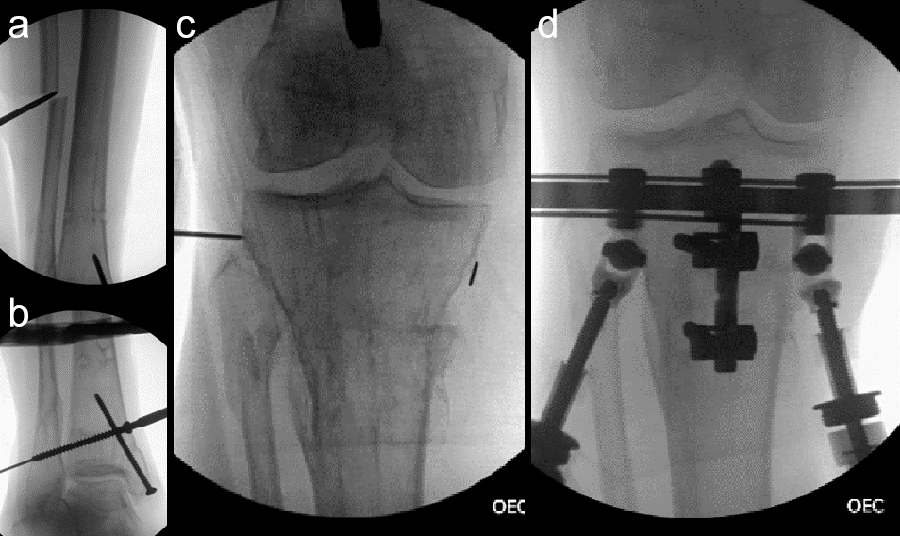

The tibial deformity was planned to be managed with a MAXFRAME AUTOSTRUT™.